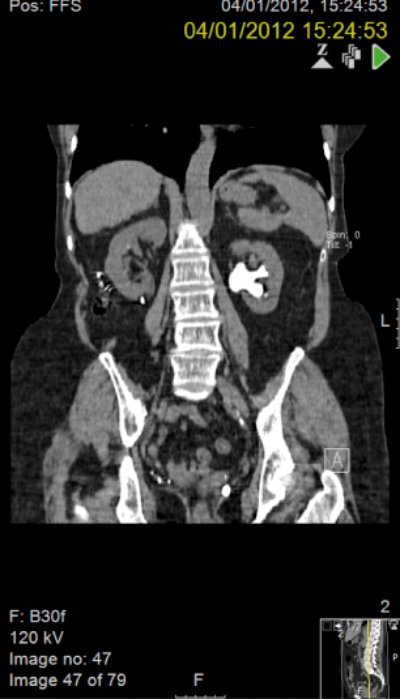

A 59-year-old woman with a right-sided duplex ureter presented with right flank pain and confirmed recurrent urinary tract infection and a right lower pole calculus lying peripherally with very little overlying cortex.

PCNL was considered but a laparoscopic approach was preferred due to the radiological lack of overlying cortex. A four-port retroperitoneal laparoscopic approach was utilised.

The patient is pain free with no further urinary tract infections postoperatively. The stone is still visible in the retroperitoneum on CT scanning but has caused no further problems 10 years on from surgery.

Preoperative IVU and CT demonstrating very little overlying renal cortex in duplex system.

Seven years postoperatively. New left staghorn calculus and right-sided fragment demonstrated outside the kidney.